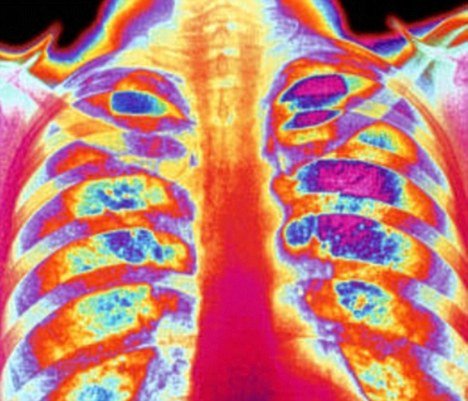

Healthy lungs contain hundreds of millions of tiny air sacs called alveoli, which help in the absorption of oxygen into the blood as well as removing carbon dioxide.

In emphysema patients, these tiny air sacs become inflamed, and in many cases are damaged and destroyed, triggering coughing and breathlessness. This is frequently due to the effects of smoking, but the condition can also affect non-smokers, either through a genetic susceptibility, or exposure to workplace chemicals.